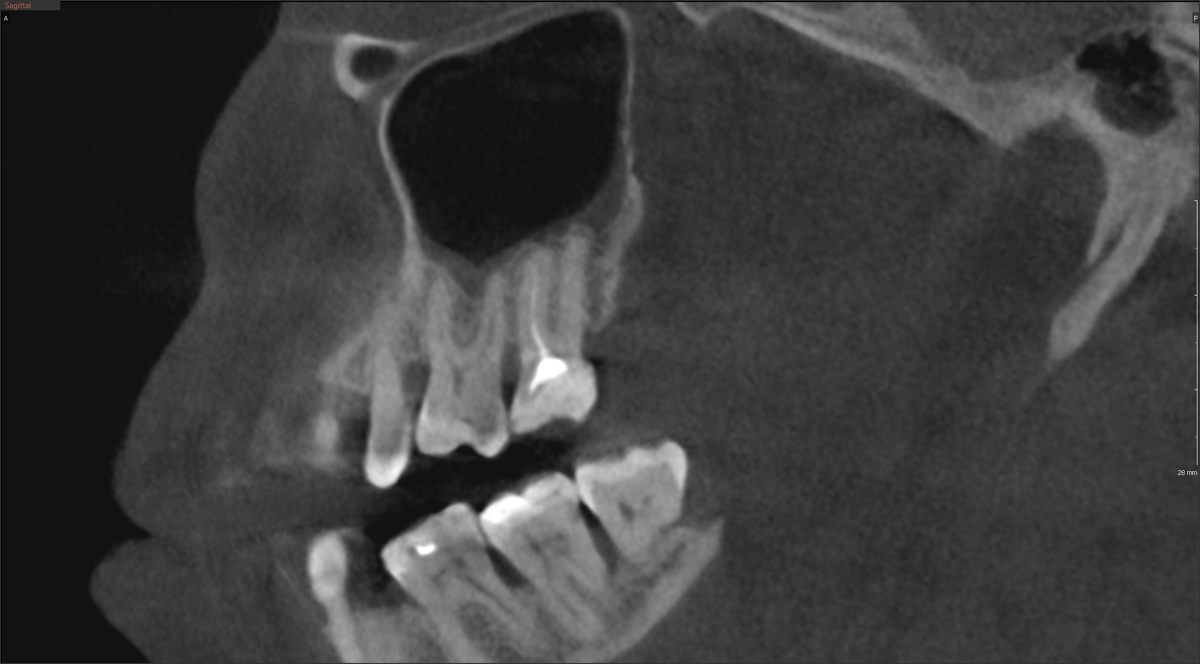

Пациентка проходит у нас лечение уже около полугода. Работа, в основном, лечебно-терапевтическя - несколько зубов уже перелечены успешно. Дошла очередь до зуба 2.7, верхней семёрки. Плановая ревизия, ничего этакого, вроде бы, нет.

Зуб , на удивление, особо не беспокоил, периапикальных изменений, практически, нет.

Со слов пациентки, зуб лечился четыре-пять лет назад.

На первый взгляд - ничего особенного. Большая пломба, тонкие стенки, небольшой кариозный процесс под пломбой. Роман Юрьевич ещё на этапе осмотра держал в голове два сценария:

У этого зуба определяются четыре канала. Нёбный и первый медиально-щёчный - были ранее найдены и запломбированы. Два других - не найдены вовсе.